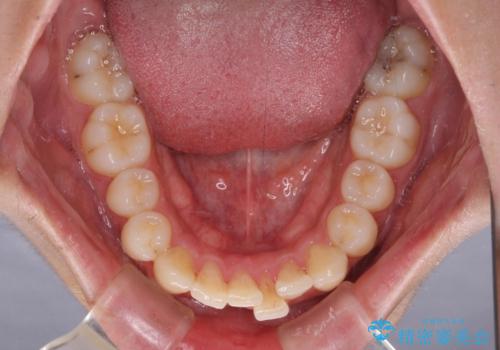

- 矯正治療の後戻りを気にして来院された患者様です。

後戻りは軽微であったので、インビザライン・ライトにより矯正治療を行うこととしました。

矯正治療後は、再度後戻りすることを極力回避するために、下顎前歯の舌側を細いワイヤーを用いて保定することとしました。